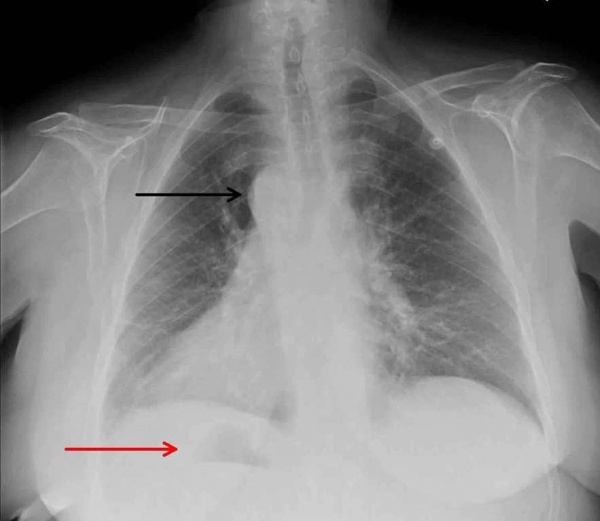

При рентгенологическом исследовании обнаружено аномальное расположение сердца: тень сердца находится преимущественно в правой половине грудной клетки, верхушка сердца ориентирована вправо (рис. 3).

- Рентгенография ОГК. На рентгенограмме визуализируется смещение сердечной тени вправо, при комбинированных аномалиях изменяются контуры магистральных сосудов. Чтобы подтвердить транспозицию проводится рентгенография органов брюшной полости.